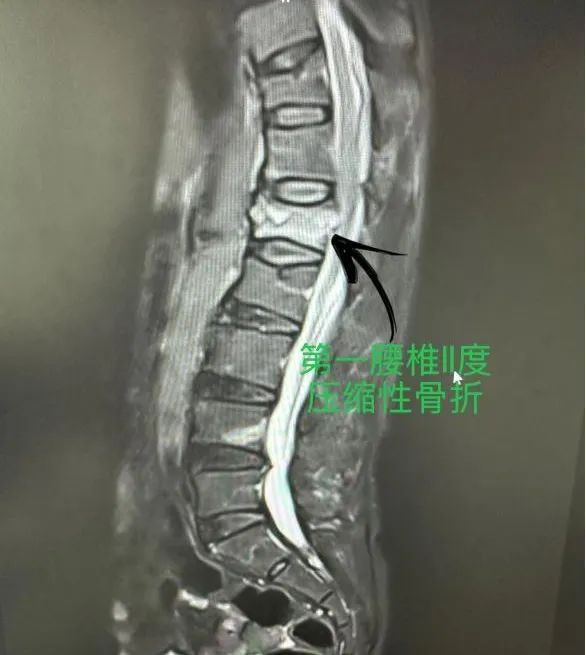

患者胡奶奶,67岁,因在家中打扫卫生不慎滑倒,当即感到腰部剧烈疼痛,无法站立和行走。为求诊治遂来我院,经磁共振检查显示,胡奶奶腰1椎体出现压缩性骨折,且患有骨质疏松,考虑传统手术创伤大、恢复慢,经过骨科医疗团队严谨的病例讨论和方案制定,最终决定为其实施经皮椎体后凸成形术(PKP)。